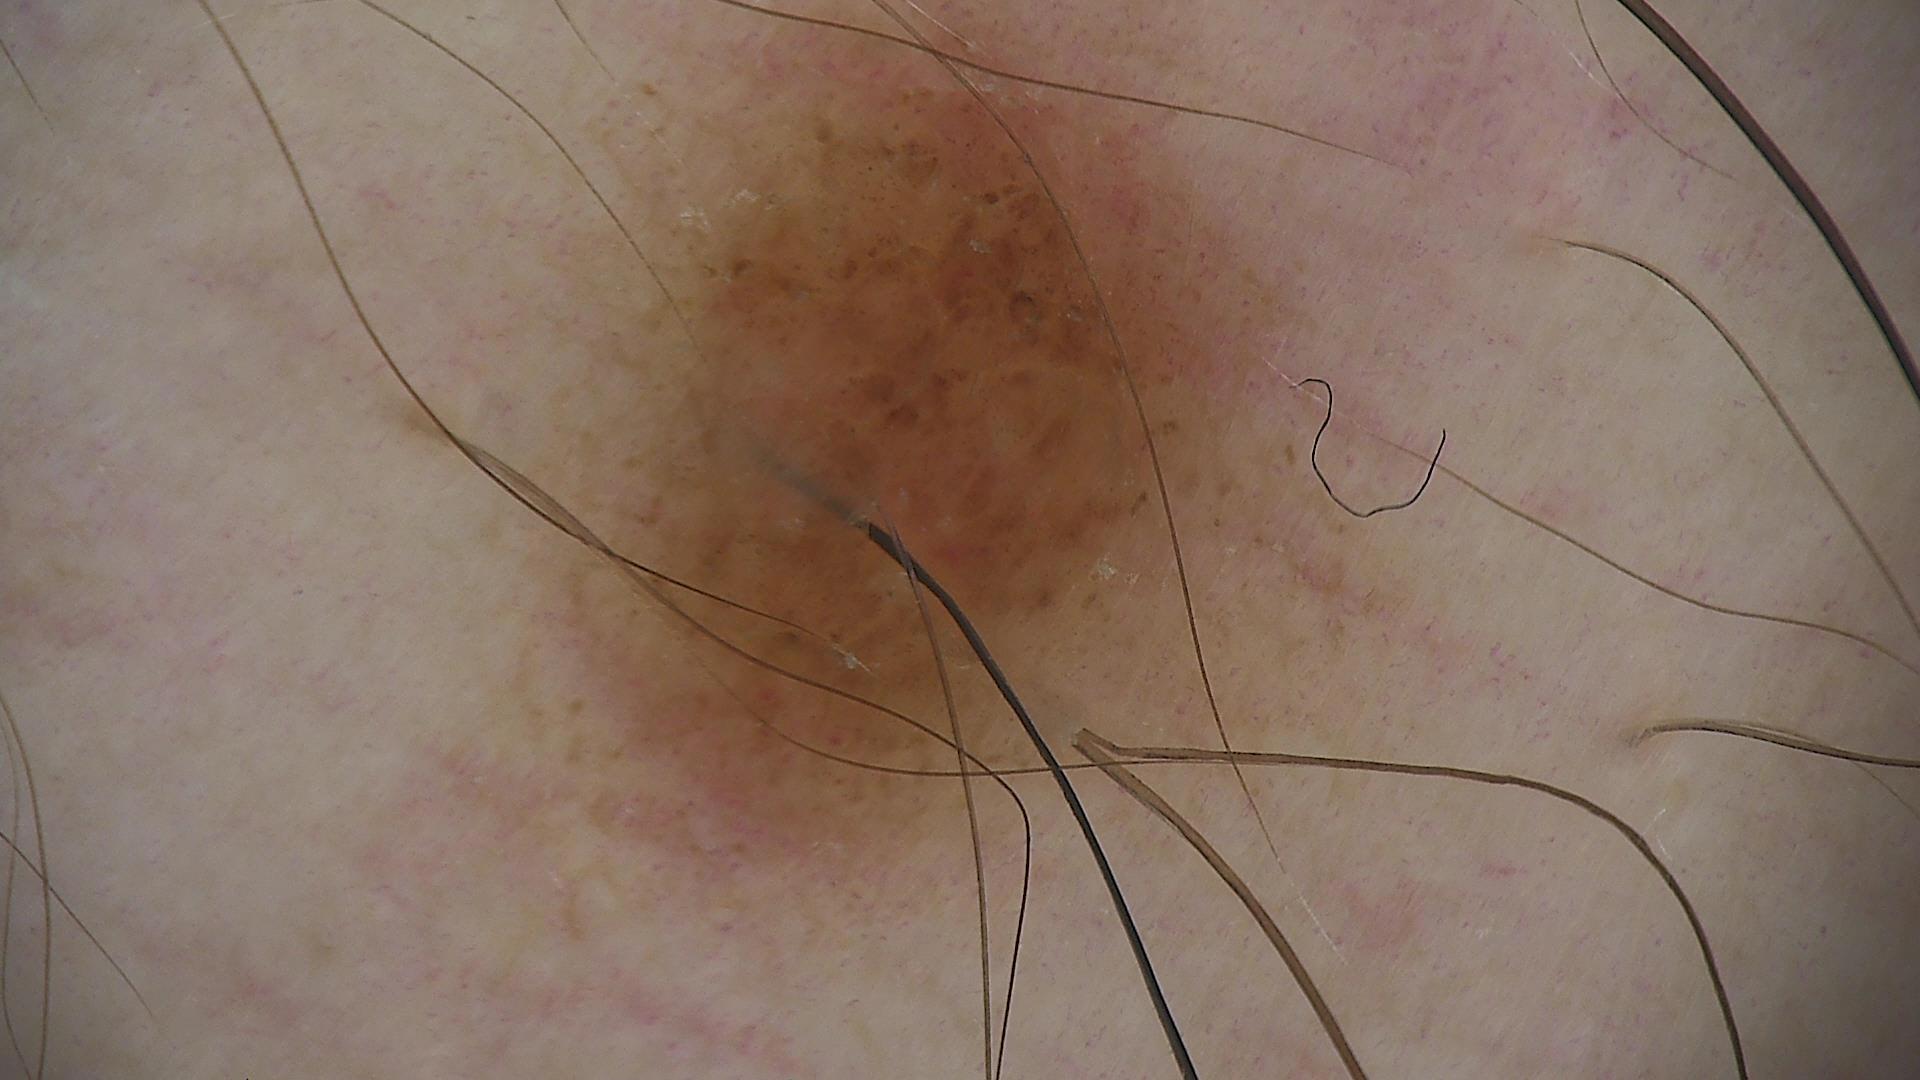

Skin lesion datasets provide essential information for understanding various skin conditions and developing effective diagnostic tools. They aid the artificial intelligence-based early detection of skin cancer, facilitate treatment planning, and contribute to medical education and research. Published large datasets have partially coverage the subclassifications of the skin lesions. This limitation highlights the need for more expansive and varied datasets to reduce false predictions and help improve the failure analysis for skin lesions. This study presents a diverse dataset comprising 12,345 dermatoscopic images with 40 subclasses of skin lesions, collected in Turkiye, which comprises different skin types in the transition zone between Europe and Asia. Each subgroup contains high-resolution images and expert annotations, providing a strong and reliable basis for future research. The detailed analysis of each subgroup provided in this study facilitates targeted research endeavors and enhances the depth of understanding regarding the skin lesions. This dataset distinguishes itself through a diverse structure with its 5 super classes, 15 main classes, 40 subclasses and 12,345 high-resolution dermatoscopic images.

Yilmaz, A., Yasar, S.P., Gencoglan, G. et al. DERM12345: A Large, Multisource Dermatoscopic Skin Lesion Dataset with 40 Subclasses. Sci Data 11, 1302 (2024). https://doi.org/10.1038/s41597-024-04104-3